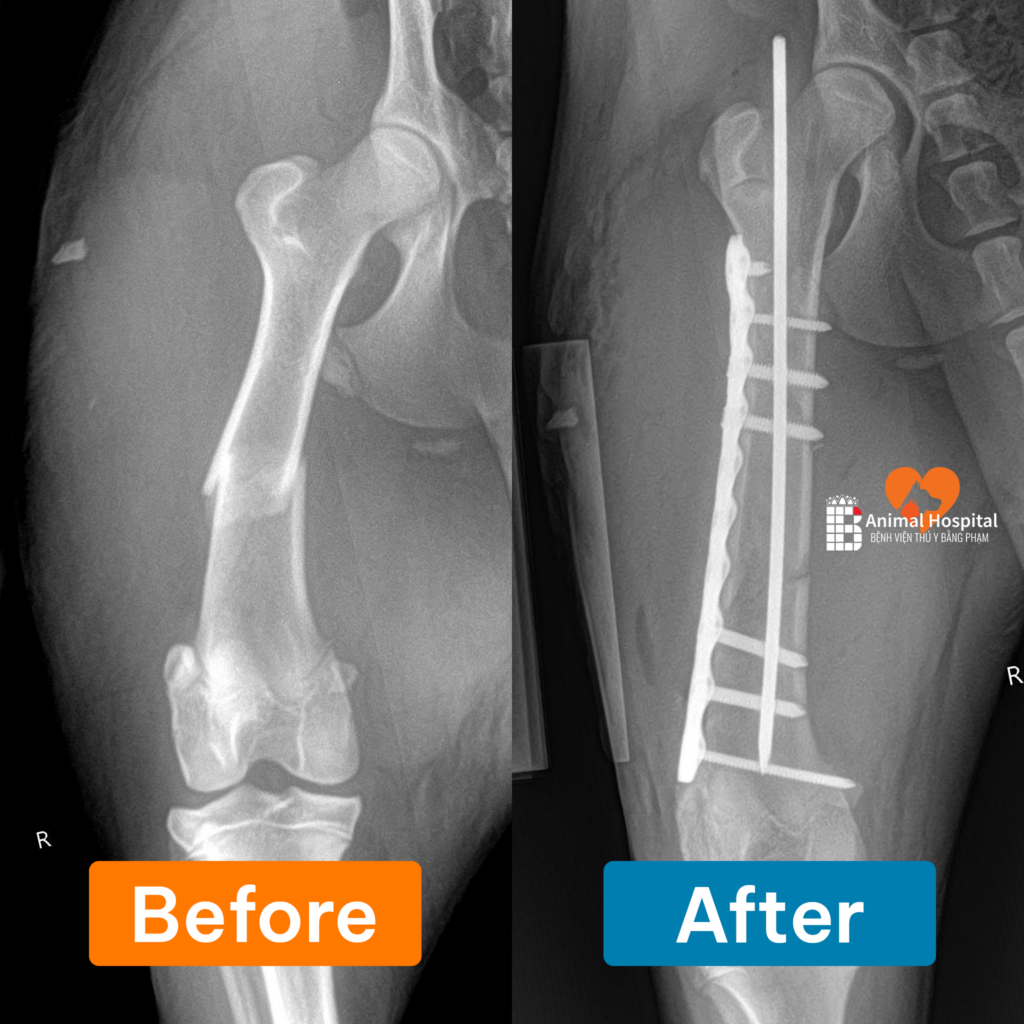

Qua thăm khám lâm sàng và hình ảnh X-quang, đội ngũ bác sĩ xác định bé bị gãy thân xương đùi (Femoral Shaft Fracture). Đây là một chấn thương nặng, đòi hỏi phải can thiệp ngoại khoa kịp thời để tránh nguy cơ tật nguyền vĩnh viễn. Sau khi được bác sĩ đánh giá và cân nhắc các phương án, chủ của Dola đã thống nhất thực hiện phẫu thuật bằng nẹp PRCL để đảm bảo khả năng phục hồi tốt nhất khi chó bị gãy xương đùi.

Điểm nhấn của ca đại phẫu là việc áp dụng hệ thống nẹp vít PRCL kết hợp đinh nội tủy. Phương pháp y khoa hiện đại này mang lại những ưu điểm vượt trội:

- Sự kết hợp này tạo nên một cấu trúc cố định vững chắc.

- Phương pháp này giảm thiểu diện tích tiếp xúc giữa nẹp và xương để bảo vệ nguồn cung cấp máu, giúp đẩy nhanh quá trình can xương.

Ca mổ kết thúc thành công với các lớp mô được khâu phục hồi thẩm mỹ.